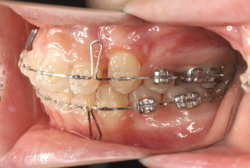

凸凹な歯並びのことを叢生といいます。矯正歯科に来院する患者様の主訴の中で、最も多いのが「配列の凸凹を真っ直ぐにしたい」というものです。歯の大きさと顎の大きさの調和がとれていないことが原因です。

凸凹を主体としたケースの場合、当院の平均治療期間は18ヶ月ですので、このケースは少し長めに経過しました。理由の一つは凸凹の程度がかなり重症だったと言うことですが、もう一つは、右下第2大臼歯が45度くらい前傾していたため、それを整直化させるために時間を要したと考えています。いずれにしても最終結果は大変よい状態と思います。

治療前は並びが乱れて見た目が悪いというのはもちろん問題ですが、歯科医学的に一番困るのは噛み合わせが悪いという点です。上下の犬歯(3番目の歯)は、上下的に離れた位置にあるため接触することができません。つまり歯としては存在していても、歯としては機能していないということです。